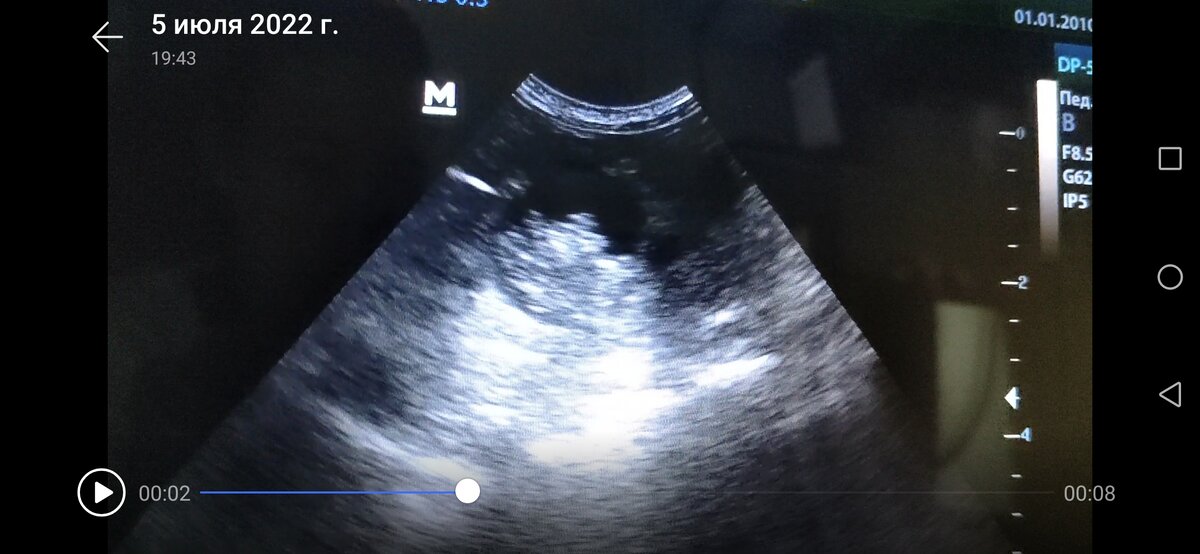

Проведено ультразвуковое исследование, которое показало интересные образования одинаковой ультразвуковой картины, но в разных местах. Одно крупное образование в проекции уретры, кажется, что даже в ее просвете, возможна частичная или полная обструкция. Размер около 2 см, с четко очерченной границей, тонкостенное образование, в полости которого видна жидкость, в на дне какое-то клеточное содержимое, движущееся при дыхании. Второе образование похожее на первое, но с дистальным усилением в области краниального полюса левой почки, возможно опухоль надпочечника. Третье образование в брюшной полости среди петель кишечника краниальнее мочевого пузыря с той же картиной и с теми же характеристиками.